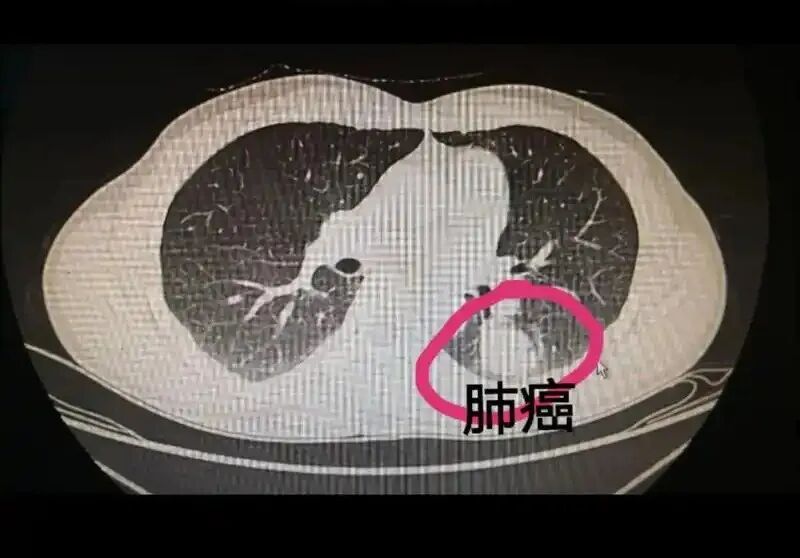

世界卫生组织(WHO)明确指出: 氡气是全球第二大肺癌致病因素(仅次于吸烟)。 对于从不吸烟的人群,氡气甚至是肺癌的第一危险因素。

📌 国际数据提示: 长期暴露于高浓度氡环境,肺癌风险可增加 1.5–2 倍以上。